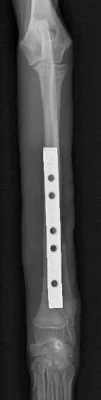

右前肢

右前肢はLag Screw固定の併用が可能だったので1期癒合

右前肢は骨片間圧迫を加えているため、骨折端同士が直接癒合します。

そのため仮骨形成が少なく、早期に癒合します。

術後19日 右前肢は治療終了です。